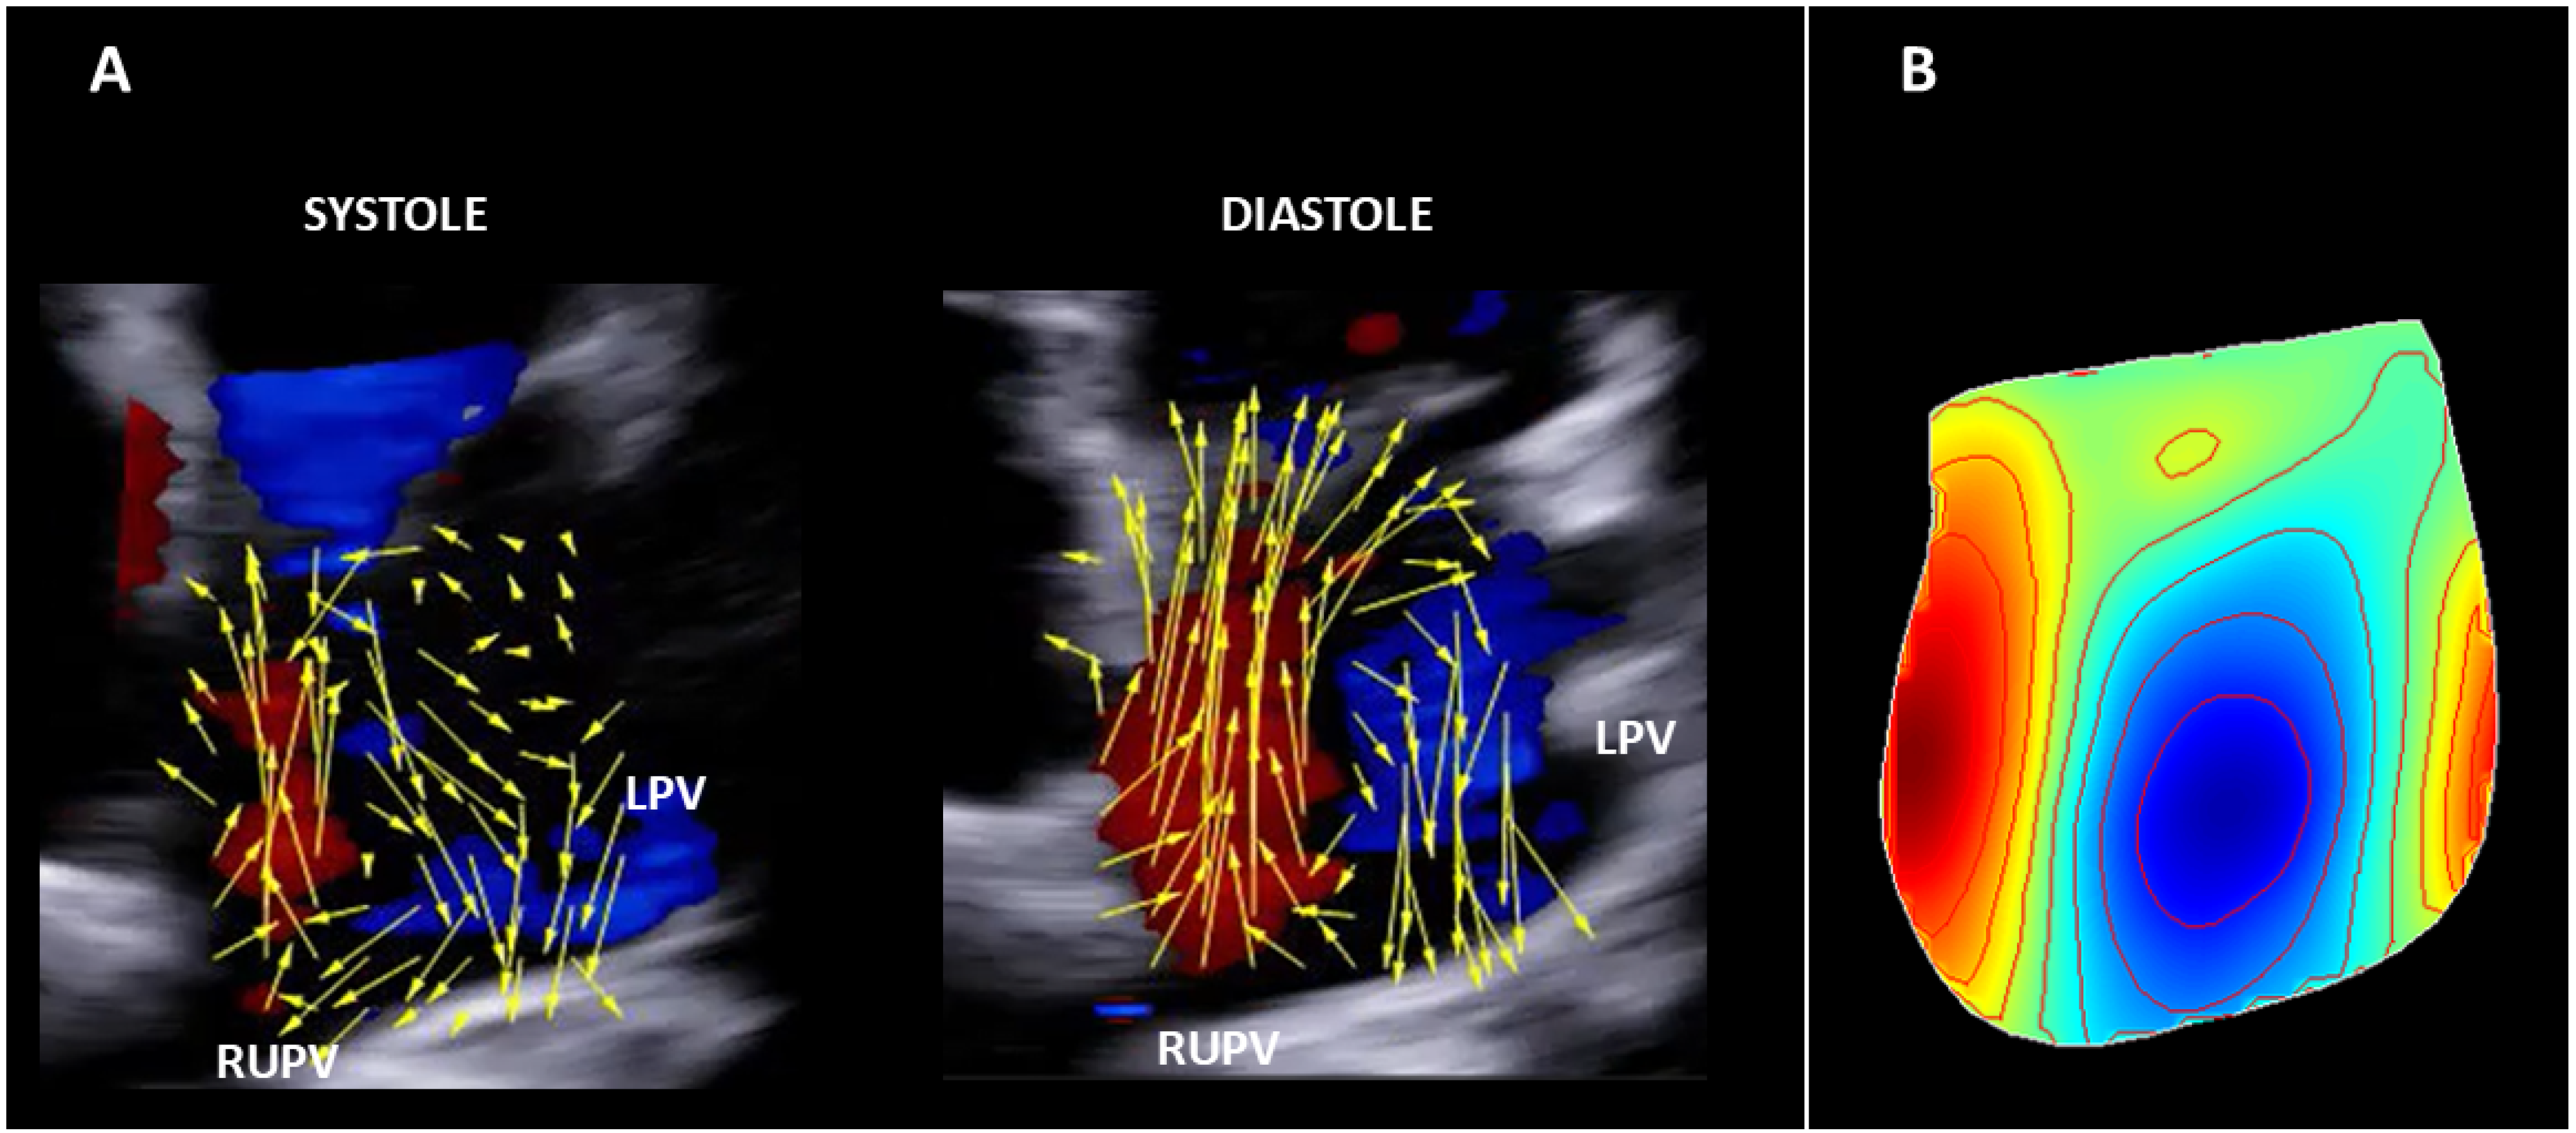

3.1.1. Healthy Subject

4.4. Current Observations